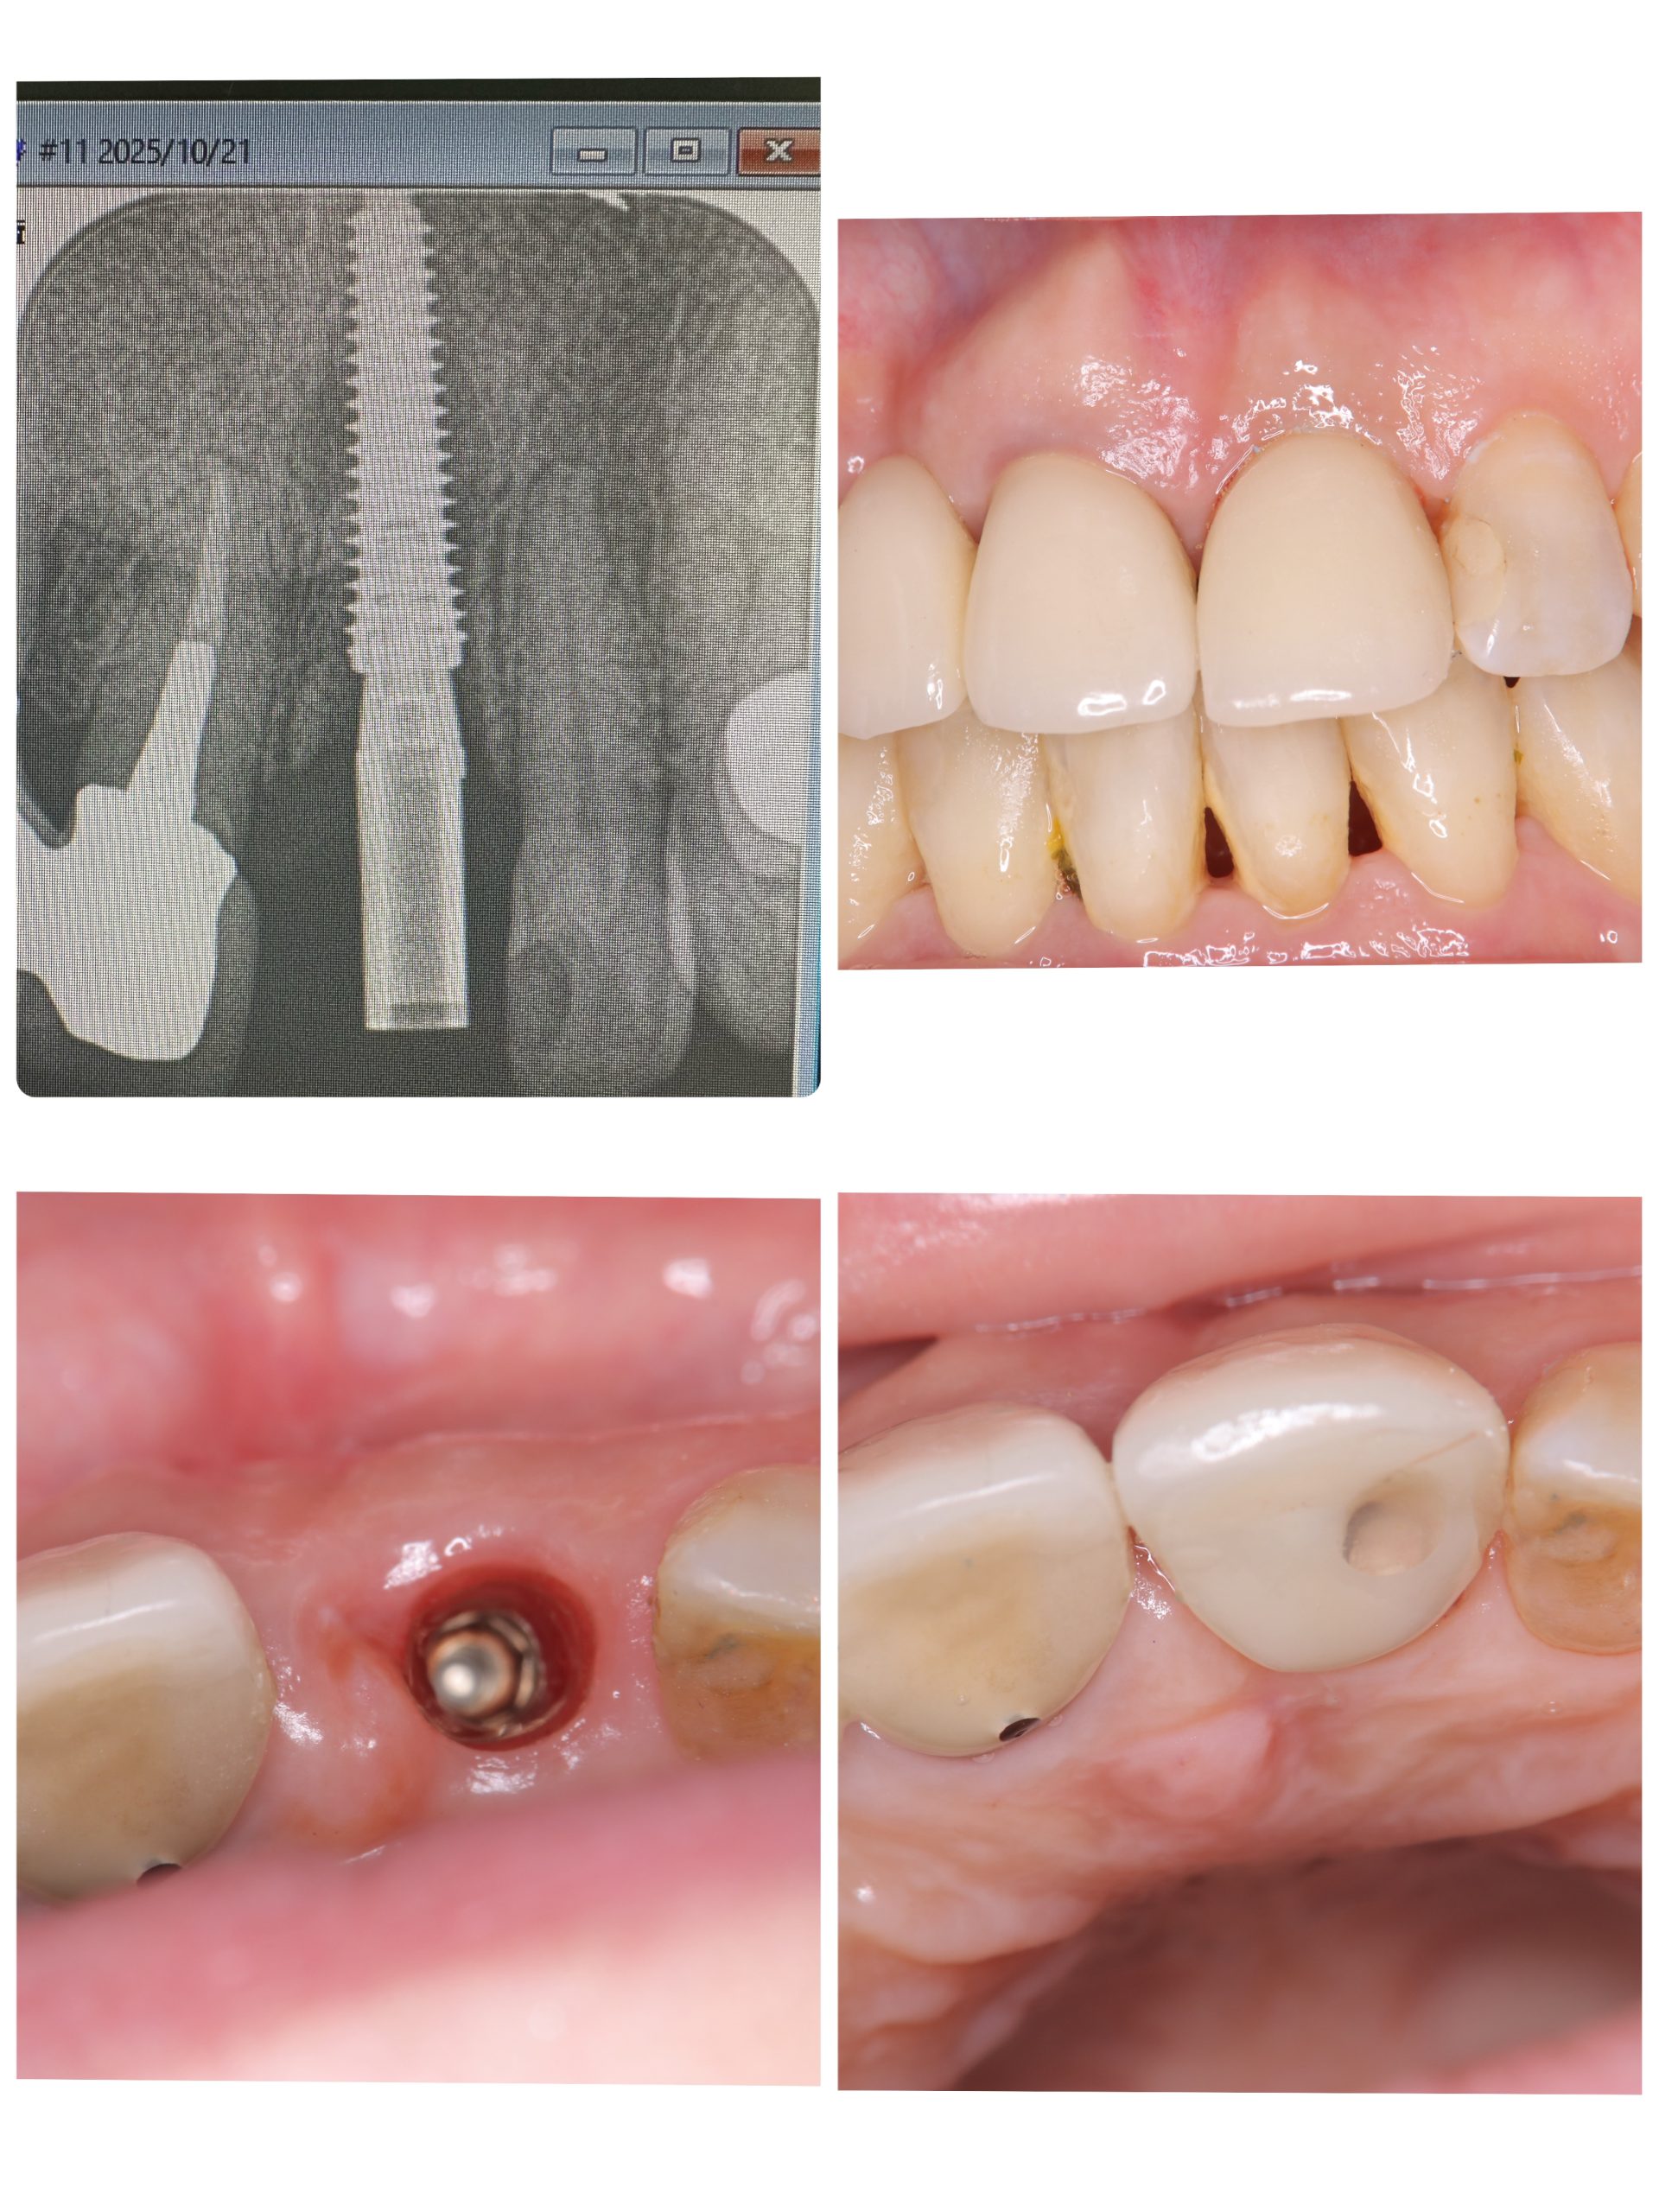

次のお方は前歯インプラントセット

次回3度締めで終わり

セミルーナフラップした方の頬側の骨再生画像確認

ソケットシールドしてるから、吸収なくボリーュミー